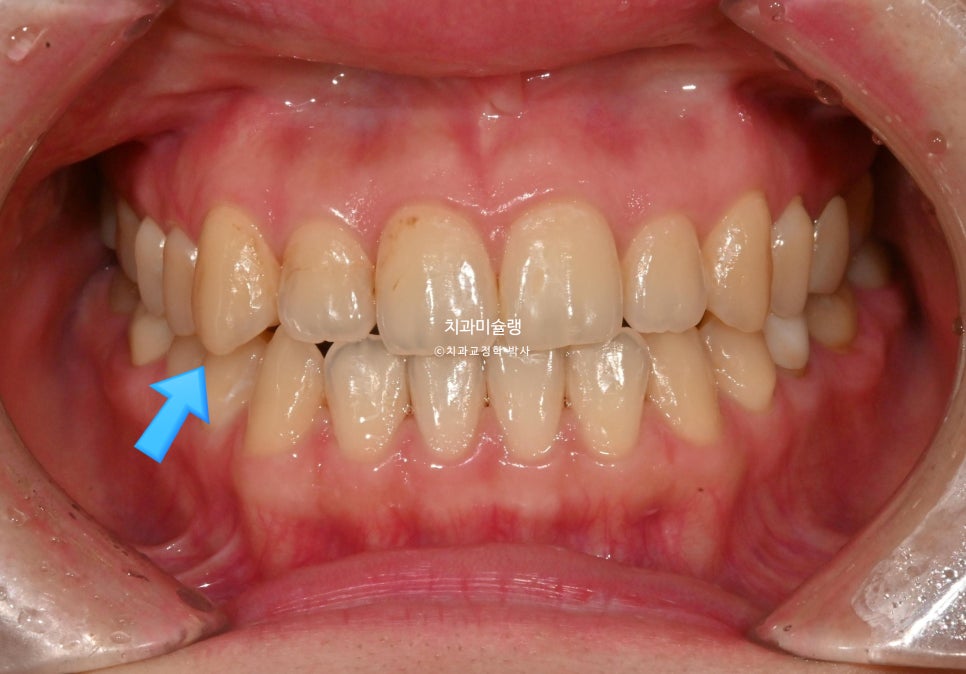

작년 9월, 말할때 앞니가 안보여서 보이게 하고싶다 는 주소로 온 30대 환자분 입니다.

우측 송곳니가 내려와있고 앞니 치축이 위아래 둘다 전반적으로 기울어져 있습니다.

치아색도 어두운 편이고 갈색 반점이 넓게 퍼져있습니다.

내려와있는 한쪽 송곳니, 기울어진 치축 때문에 비대칭의 느낌이 있습니다.

말할때 윗니가 잘 안보이며 입술이 얇고 볼륨감이 적은편입니다. 웃을때도 치아가 그림자져 보입니다.